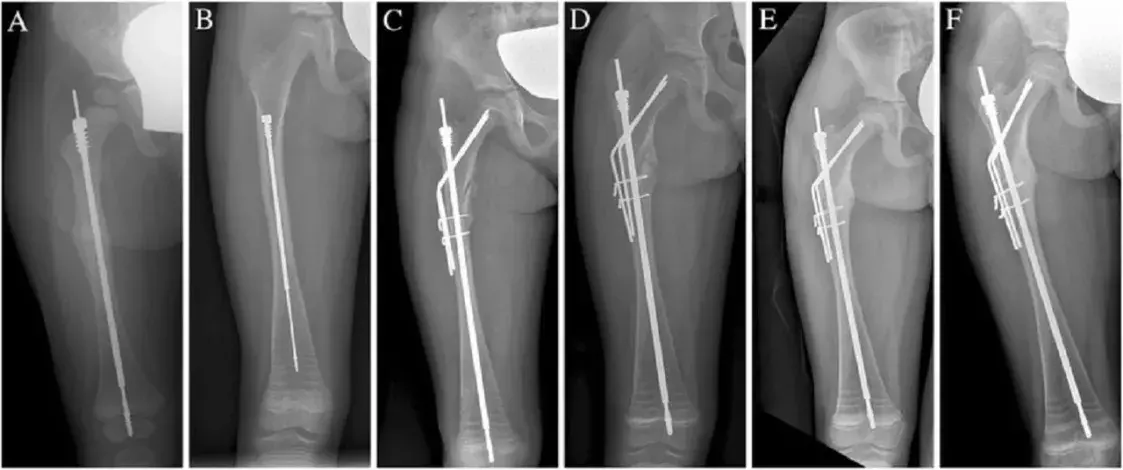

Рентгенограмма правой бедренной кости, на которой виден стержень Fassier-Duval / researchgate.net

Так, а что там с отечественными “Fassier-Duval”?

Пациентам такой вариант не предлагают и не будут предлагать ещё очень долго. Прототип есть, но почему дело не движется далее — мне непонятно. Да, это очень технологическое изделие, и просто копия запатентованного изделия тоже подошла бы.